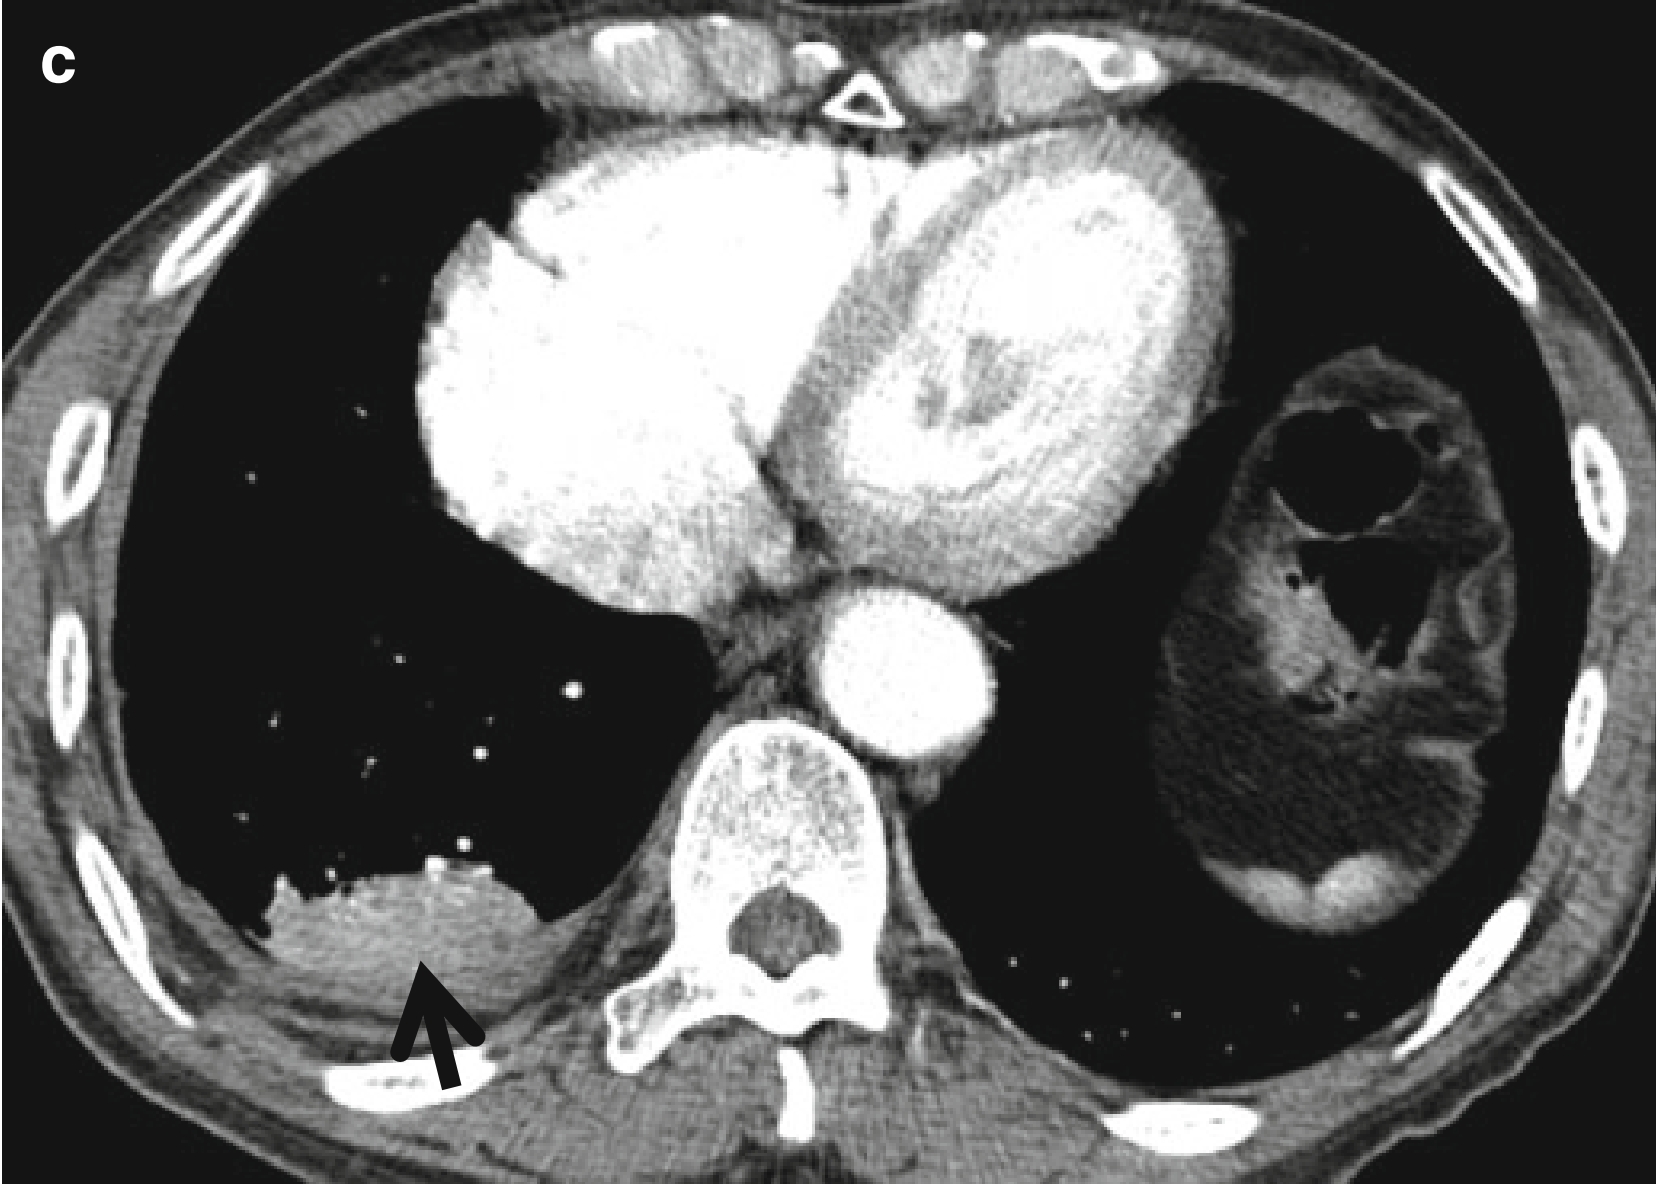

男,66岁,主诉气促和咳嗽。

(c)纵隔窗可见不张的肺组织强化(箭头所示)。